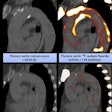

NaF-PET scans reveal plaque -- and possible risk of stroke